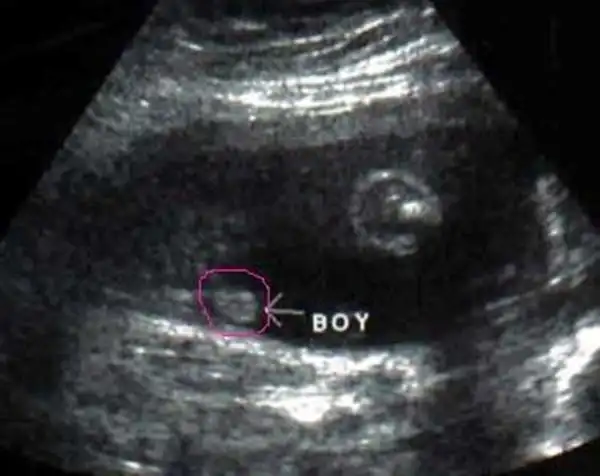

男胎儿小鸡四维显示图b超图看胎儿性别图解